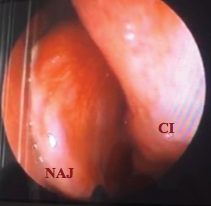

En el consultorio se realizó nasofibrolaringoscopia observándose masa pálida dependiente del cornete medio izquierdo en alto contacto con el cornete inferior izquierdo (Figura 4)

![NAJ Nasoangiofibroma Juvenil. CI[Cornete inferior]](../273856494018_gf6.png)